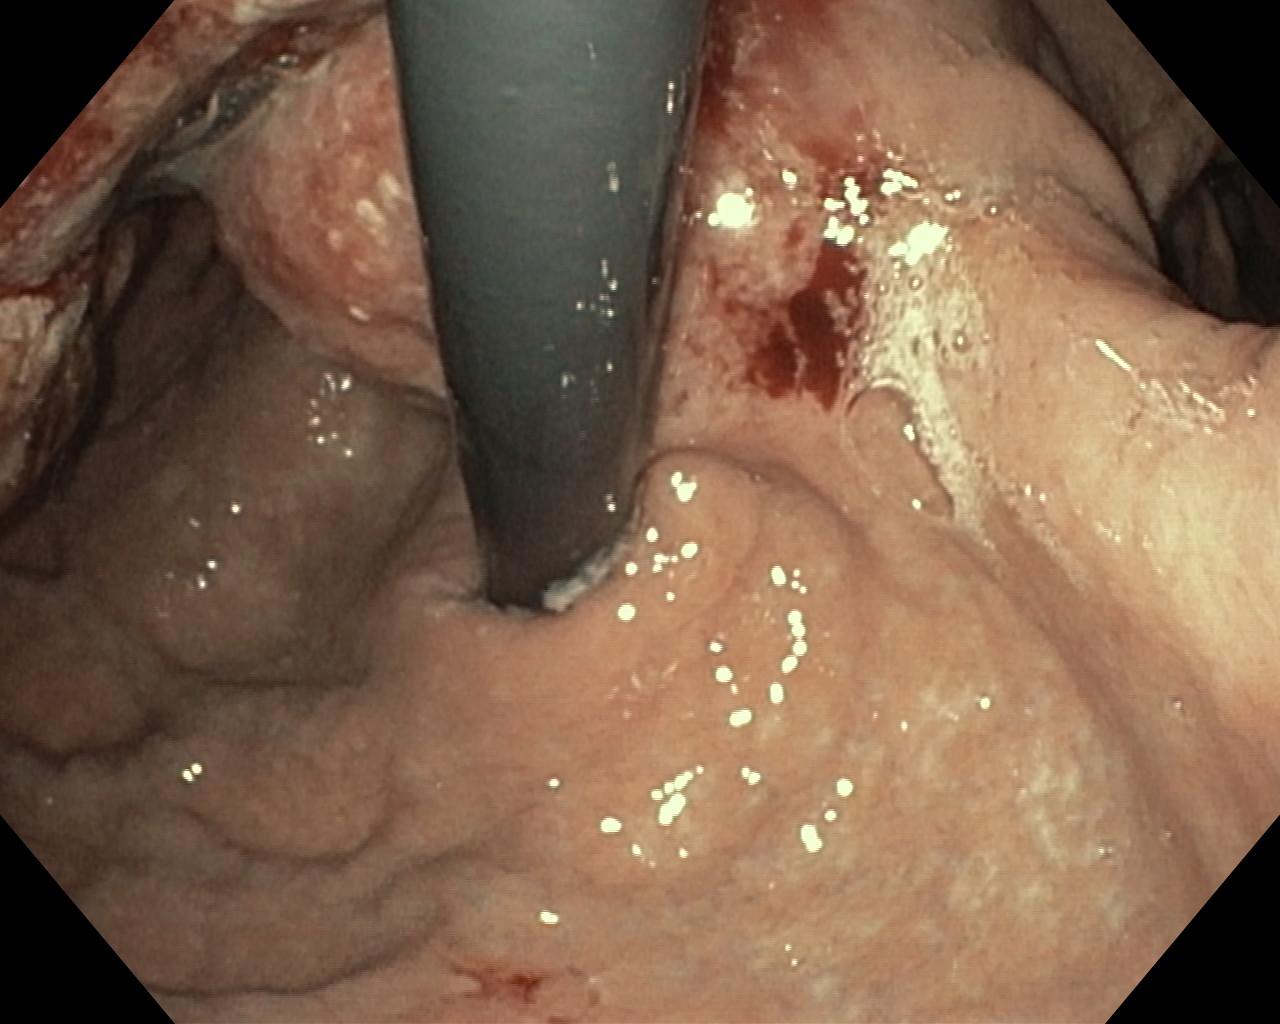

Obrazy endoskopowe

Nowotwory przewodu pokarmowego